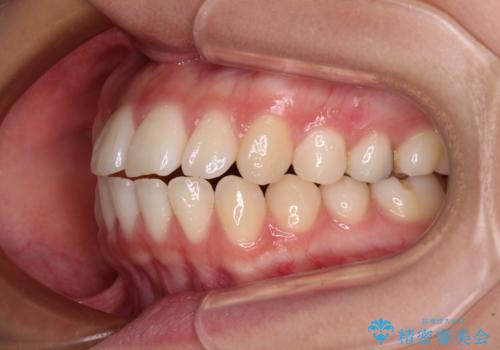

横顔の印象を変えたい ワイヤー装置での抜歯矯正

- 口元の突出感と上下前歯のズレを気にして来院された患者様です。

舌の突出癖により上下の前歯は非接触となっている状態でした。

舌のトレーニングを行わないと上下前歯の接触達成は困難であるため、トレーニングをしっかりと行っていただきながら、治療を進めて行くこととしました。

突出感改善のため、上下左右の第一小臼歯4本を抜歯し、ワイヤー装置にて矯正治療を行うこととしました。

舌のトレーニングをしっかりと行ってくださり、予定通りの期間で理想的な仕上がりを達成することができました。